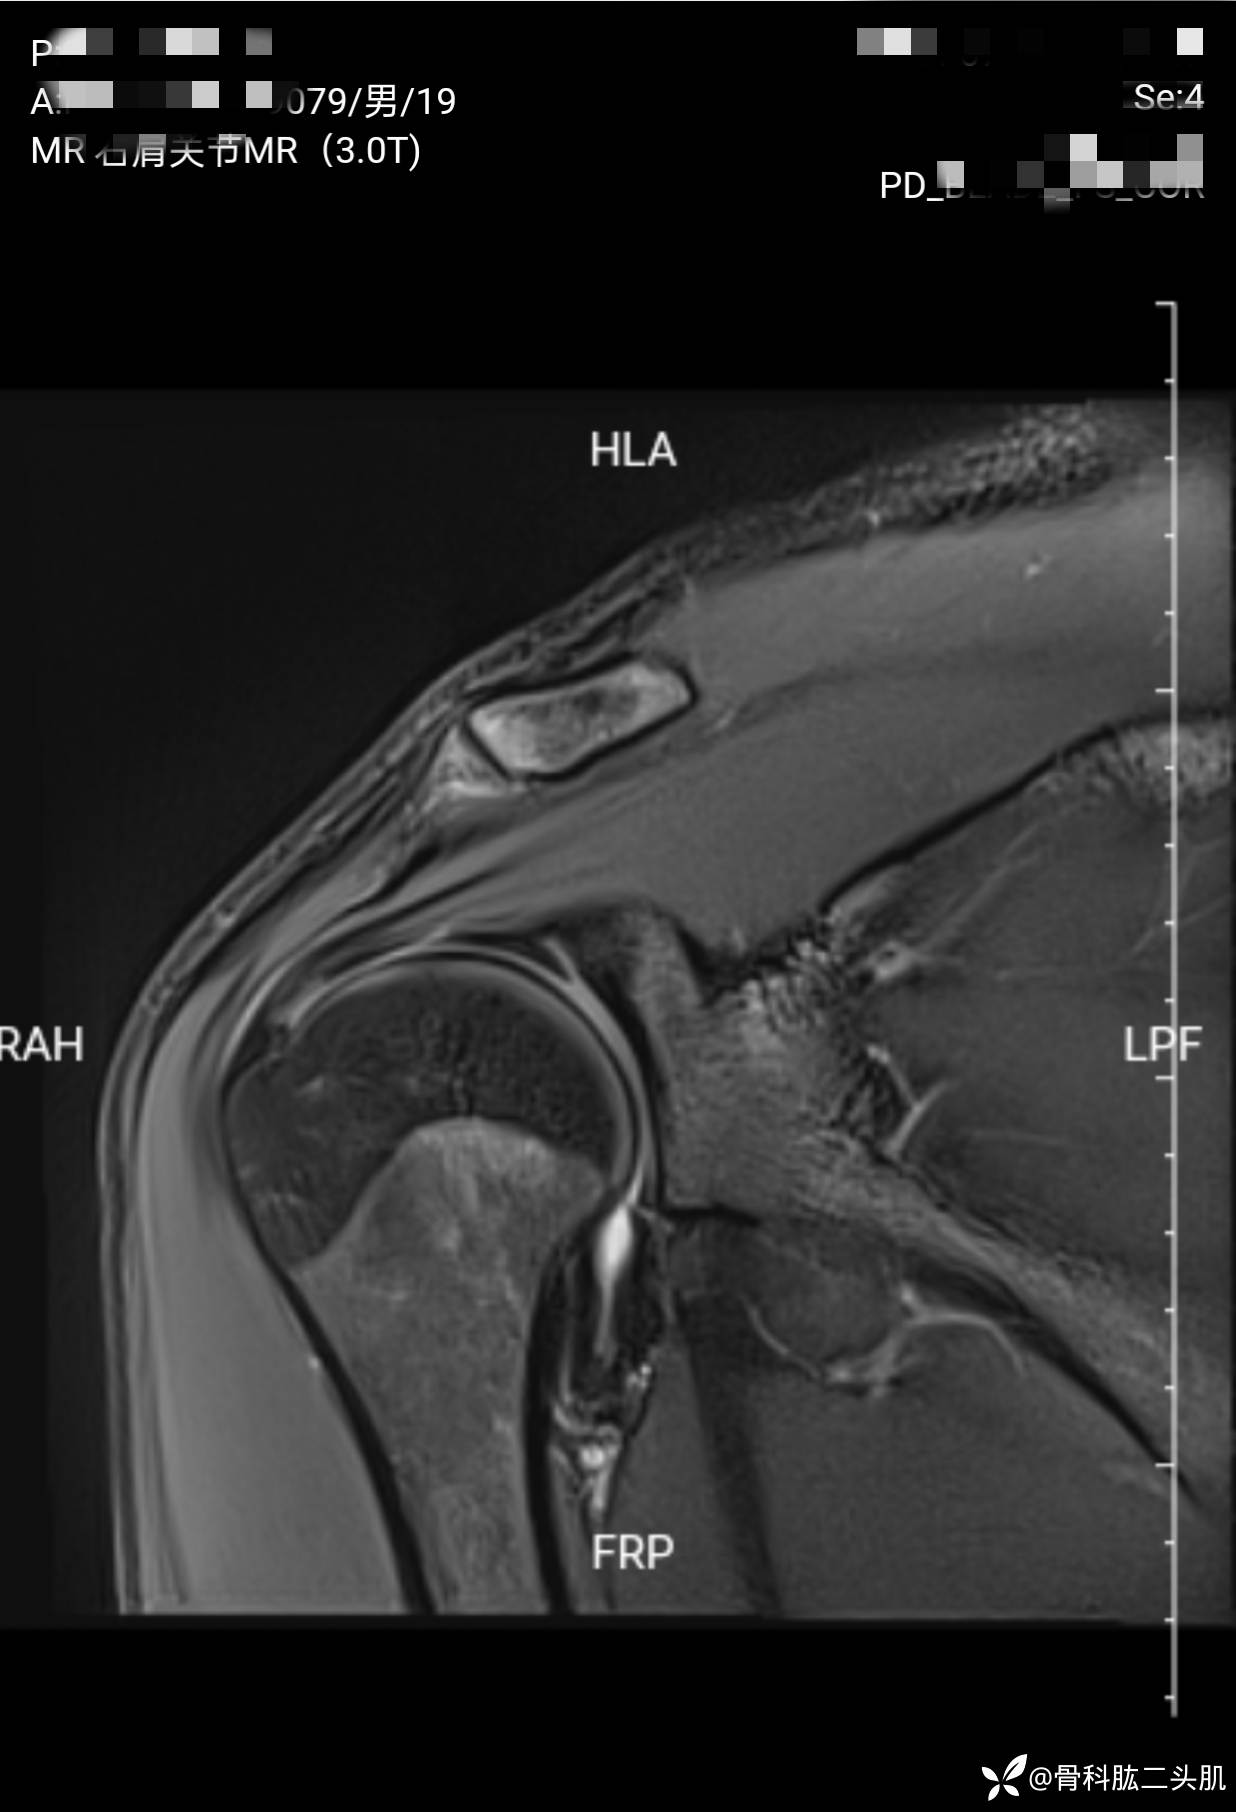

【患者信息】:患者男19岁

【主诉】:右肩关节复发性脱位2年

【检查】:外院核磁示 :右肩前盂唇及上盂唇损伤可能;右肩肱骨头后上缘骨质凹陷;右肩冈上肌肌腱损伤。

【临床诊断】:1.右肩关节复发性脱位 2 .右肩盂唇bankart损伤 3.右侧肱骨Hill—sachs损伤